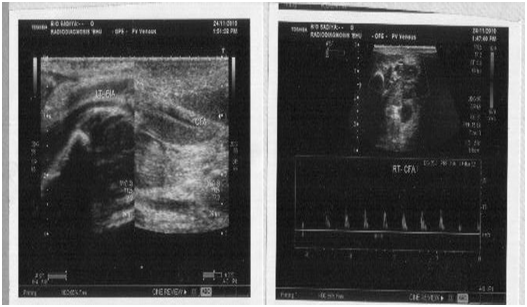

His hemogram revealed Hb: 10.8 gm/dl, TLC:15,000/mm3, DLC: N76,L20,E3,M1 and Platelet: 140,000/mm3. His renal and liver function tests were normal. There was no evidence of hemolysis in peripheral smear with reticulocyte count less than 0.5% and negative coomb’s test. His c-reactive protein was 0.91 mg/L (non-significant) and aerobic blood culture was sterile. Prothrombin and activated partial thromboplastin time were normal. Test for anti-cardiolipin antibodies [IgG:6 GPLU/mL(N:<10), IgM MPLU/mL(N:<10) and anti-thrombin III:24.4mg/dL (normal range:19-39 mg/dL) were negative. Serum protein-C was 77.8% of normal (deficiency<if less than 60%) and protein-S: 91.7% (deficiency<if less than 70%) was within normal limit. Factor V mutation analysis revealed no abnormality. Colour Doppler study of lower limb showed uncompressible common iliac vein with echogenic lumen and no evidence of flow, suggestive of left common iliac vein thrombosis, extending up to superficial femoral vein (Figure 2).

Figure 2 USG showing left common iliac vein thrombosis.